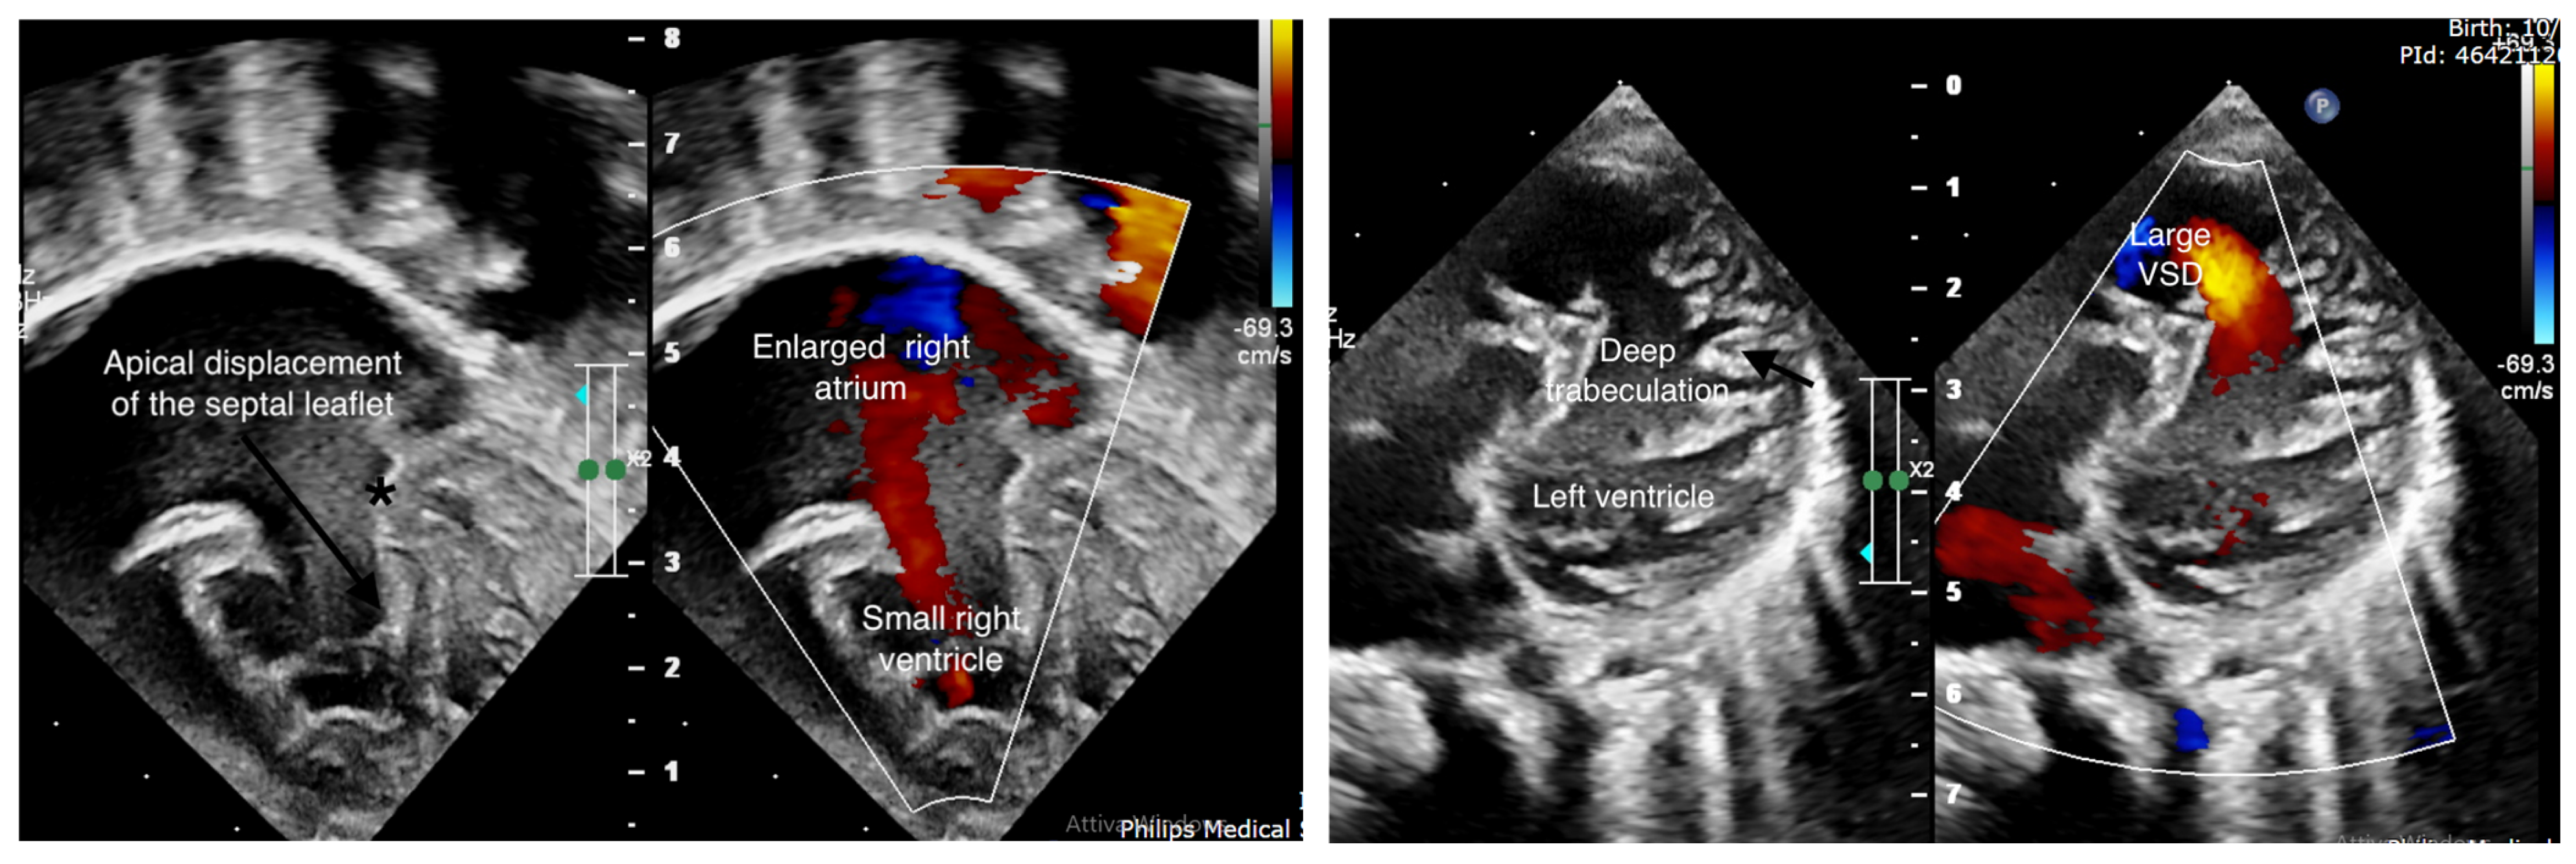

TNNC1 Gene Mutation in Ebstein’s Anomaly and Left Ventricular Hypertrabeculation: A Case Report of a New Causative Mutation?

2. Case Report